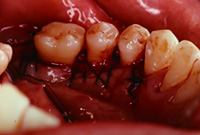

手術時

写真左から右へ手術手順です。

歯ぐきを開けると歯の周りに骨の溶けた部分が見られます。(→)はぎしりで膨れた不用な骨の部分を削ります。(→)

はぎしりで膨れた不用な骨を削ったところです。(→)